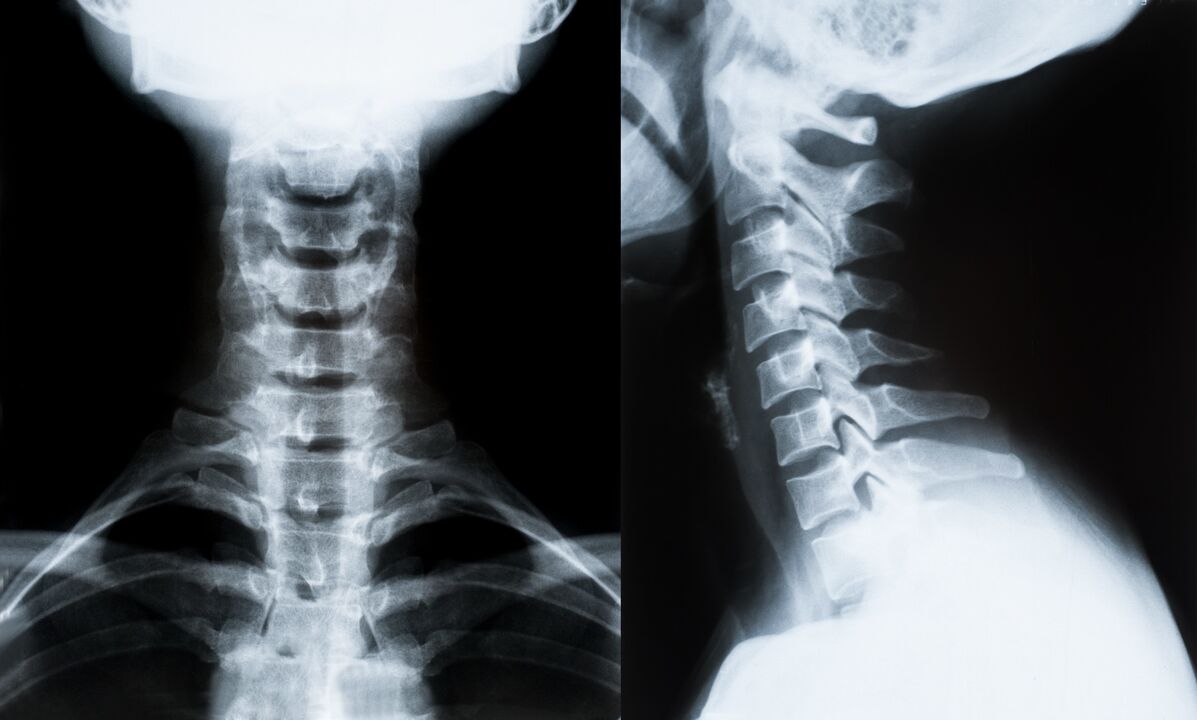

Die wichtigsten Methoden zur Diagnose und weiteren Bestimmung der Behandlung der Osteochondrose der Halswirbelsäule:

- Radiographie. Die am wenigsten wirksame, aber traditionelle Diagnosemethode.

- Die MRT ist die effektivste Diagnosemethode. Bei dieser Art der Untersuchung des Patienten sind alle notwendigen Strukturen sichtbar.

- Müssen Veränderungen gemessen werden, kommt die Computertomographie zum Einsatz. Bestimmt das Vorhandensein von Hernien und anderen Dingen.

- Die letzte Methode ist Duplex-Ultraschall. Diese Forschungsmethode bestimmt die Geschwindigkeit des Blutflusses in den Arterien.